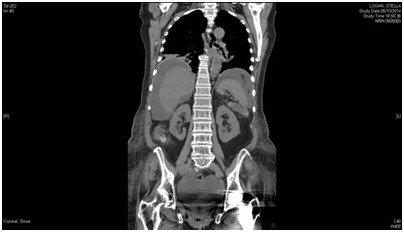

We describe gallstones at the terminal ileum, in a patient presenting with an acute small bowel obstruction, with advanced malignancy of unknown origin. CT scan images (Figures 1 & Figure 2) in our patient revealed radio-opaque stones in the gallbladder and the terminal ileum with pneumobilia and small bowel obstruction (Rigler’s triad). There was also malignant ascitis with omental metastasis from cancer of unknown primary. Patient was resuscitated and given the option of emergency surgery. But as she had advanced malignancy with poor performance status, after discussion with her and her relatives, she was managed conservatively and no further active surgical intervention was advocated.

Figure 1 CT scan showing radio-opaque gallstones and also a speck of radio-opaque shadow in the terminal ileum along with massive ascitis.

Figure 2 CT scan depicting the gallstone at the terminal ileum causing clinical small bowel obstruction.